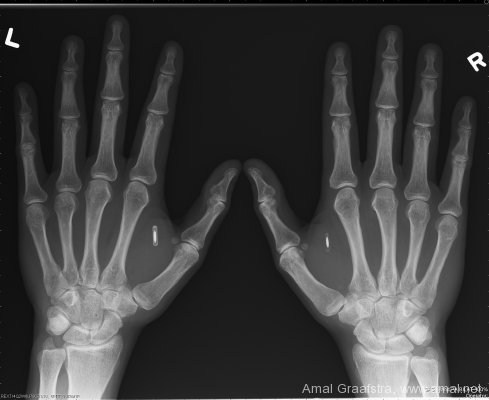

Размеры чипа и место имплантации: